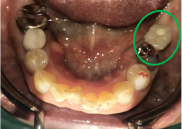

左下、ブリッジの支台になっていた奥のほうを抜歯したままになっている。ここのところを何とかしたい。

ブリッジの奥に伸びていた部分を削り取り、インプラントを2本入れました。

左下ブリッジのところを切り離し、奥を抜歯したままになっていました。このままでは、ブリッジの前方の支台になっていた歯に負担がかかり、将来抜歯になる可能性があることをお話ししました。歯がないところを補う方法には、部分入れ歯かインプラントがあることを説明すると、自分の歯と同じ感覚で食事ができるインプラントを選択されました。X-Guideを使用し埋入しました。口を大きく開けることができない方でしたので、X-Guideの長所のうちの一つを活かすことができました。

Before

青丸の部分を削り取りました